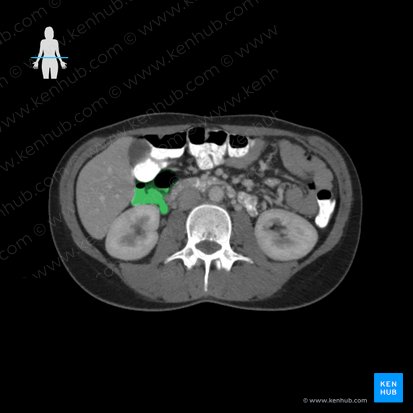

Colon ascendente

La porción del intestino grueso ubicada entre el ciego y el recto se denomina colon. Consta de cuatro partes; ascendente, transverso, descendente y sigmoide. Las principales funciones del colon incluyen la reabsorción de líquidos y electrolitos. Además, la microflora genera energía a través de un proceso llamado fermentación.

El colon ascendente viaja a través de la fosa ilíaca derecha, flanco derecho y la región del hipocondrio derecha. Termina en la flexura cólica derecha (hepática). El colon ascendente es retroperitoneal y está conectado a la pared abdominal posterior por la fascia de Toldt. Un surco o receso vertical profundo (canalón paracólico derecho) se encuentra entre el colon ascendente y la pared abdominal lateral.

El colon ascendente está involucrado en la reabsorción de líquidos y electrolitos, formando gradualmente materia fecal.